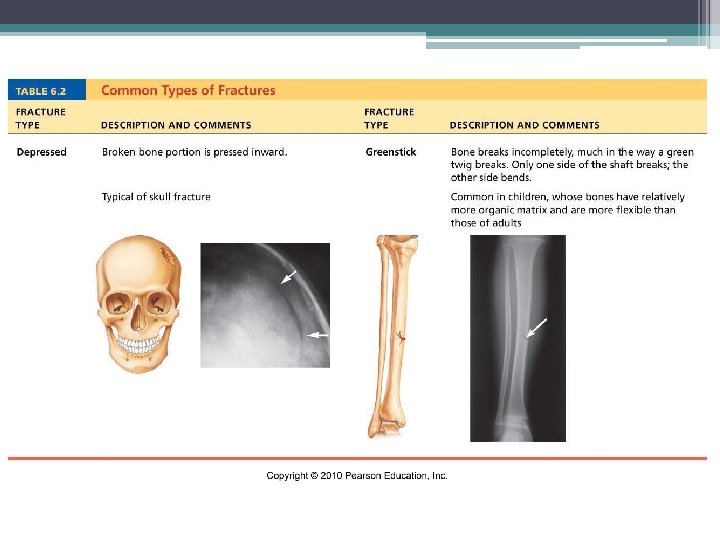

Fractures (Breaks) Classified by: 1. Position of bone – nondisplaced (normal) or displaced (bone out of alignment) 2. Completeness of break – complete (broken through) or incomplete 3. Orientation to long axis of bone – linear (parallel to bone) or transverse (perpendicular to bone) 4. If bone penetrates skin – open (compound) fracture or closed (simple) fracture